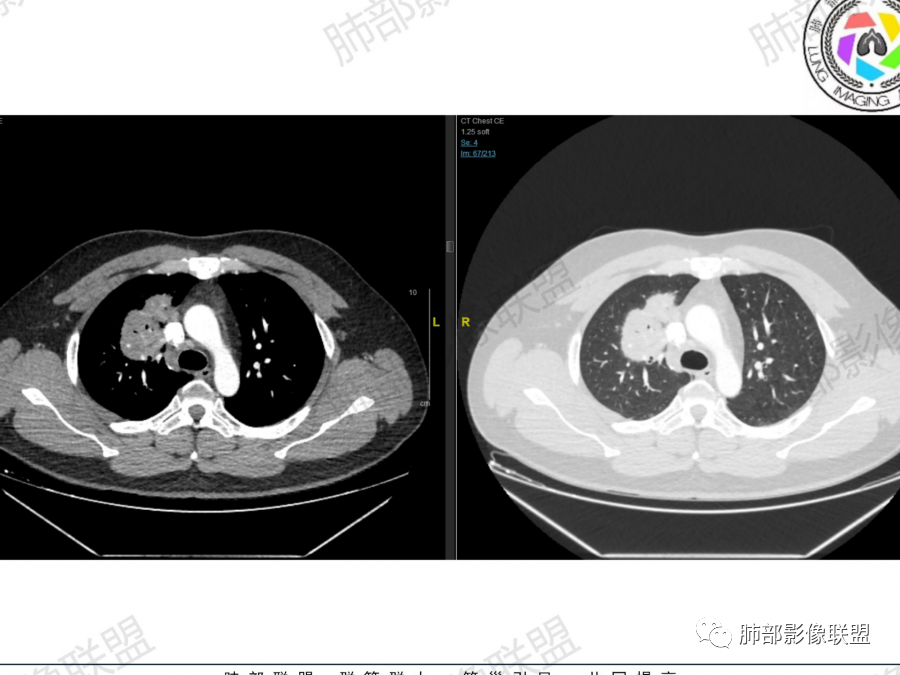

晨读:青年男性。咳嗽气喘1月,胸部ct:右肺多发结节、肿块,沿着支气管血管束及胸膜下分布,边缘平直,清楚,内支气管基本通畅、轻微扩张,血管走形自然。考虑淋巴增殖性病变,淋巴瘤?注意鉴别血管炎、隐球菌病。

晨读,青年男性,咳嗽气喘病史,铁蛋白及D2聚体升高,右肺多发病灶,上叶团块影,深分叶,不均匀强化,可见血管征,支气管充气征,走形自然。右肺下叶背段球形阴影,有融合趋势,可见空洞,洞壁光滑,有血管自然通过,下叶外侧段靠近胸膜球形阴影,有血管进入,总体恶性证据多,淋巴瘤首选。

晨读:男性,37岁,咳嗽、气喘1月,加重2天。胸部CT:右肺上叶尖段、右下叶胸膜下和支气管树周围多发结节影、大片实变(由多结节融合形成),部分边界较清、部分周围模糊晕,病灶内悬浮空泡、支气管充气征、部分支气管进入后堵塞,血管漂浮,密度较均匀,综合考虑:隐球?鉴别淋巴增殖类病变。